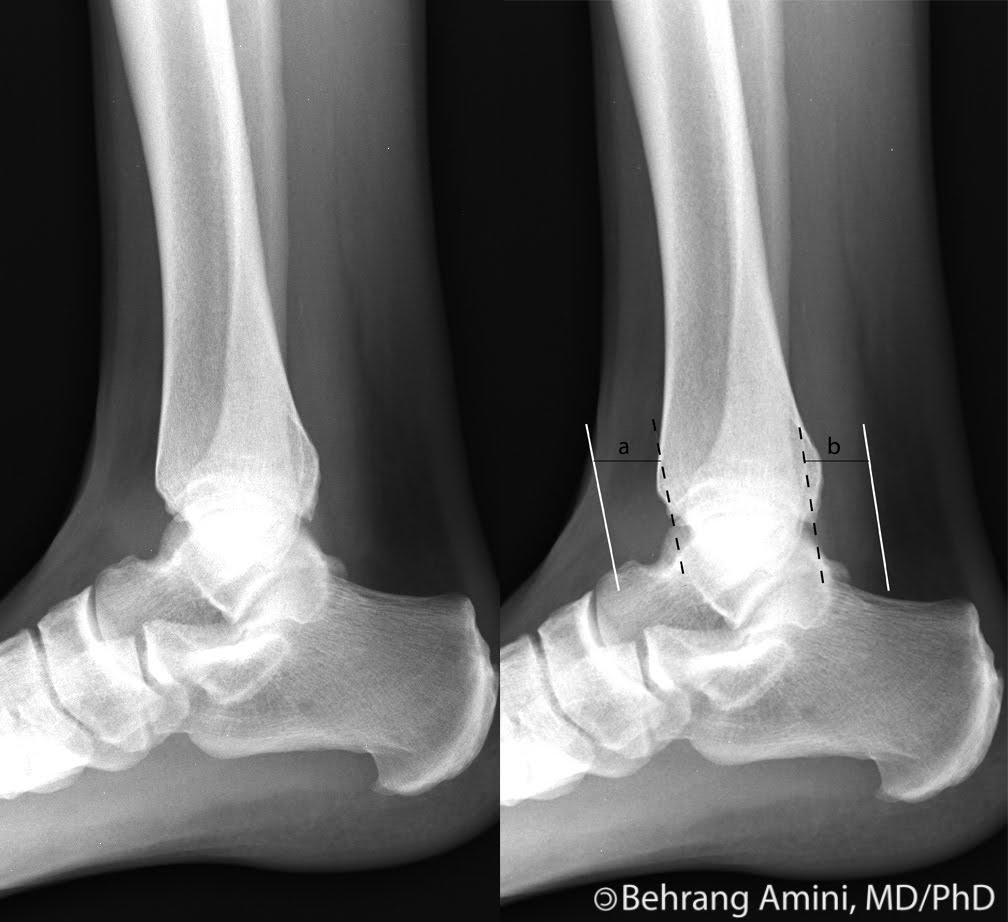

Tibiotalardiffused intraarticular effusion, fluid collection in

Tibiotalardiffused intraarticular effusion, fluid collection in Joint Effusion Treatment Ankle If the swelling is severe, your provider may want to aspirate the joint to reduce pressure. There are several approaches to treating ankle joint effusion after the reason has been. It is an inflammation of the synovium that causes pain and. How do you treat joint effusion? Treatment for effusion is based on the cause, and not all joint effusion. Joint Effusion Treatment Ankle.